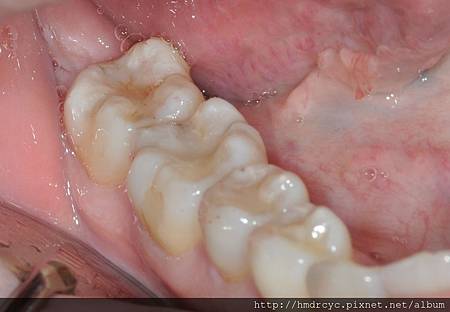

去除銀粉改為樹脂美觀填補

因為術前評估得宜

治療後咬合適應快

完全未出現敏感現象

換掉銀粉填補